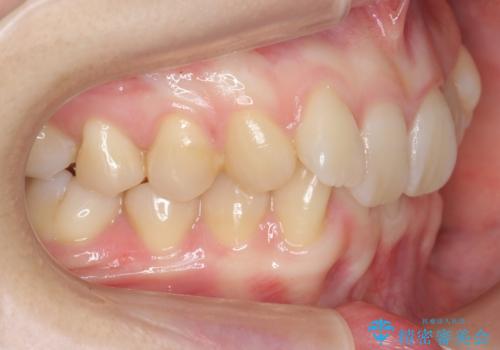

左上の犬歯が入りきらずねじれており、かみ合わせもずれていました。

左上の小臼歯を1本抜いて治療しています。

前歯は内側に傾いており(ラビッティング)、過蓋咬合(深いかみ合わせ)を呈していました。

難しい治療でしたが綺麗に咬み合わせることができ、また前歯もしっかり当たるように治療できました。